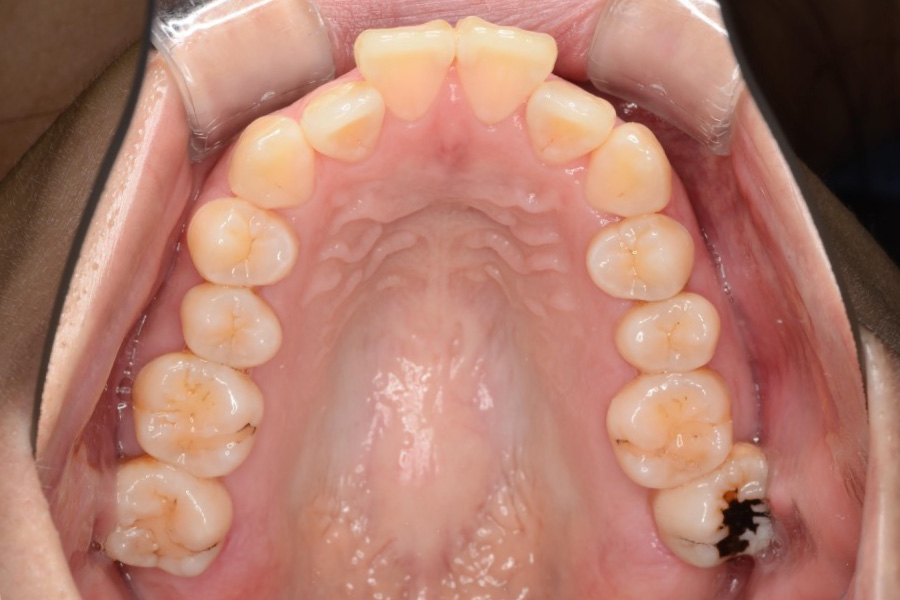

治療前

主訴 歯のガタつき

治療内容 インビザライン矯正

小臼歯抜歯